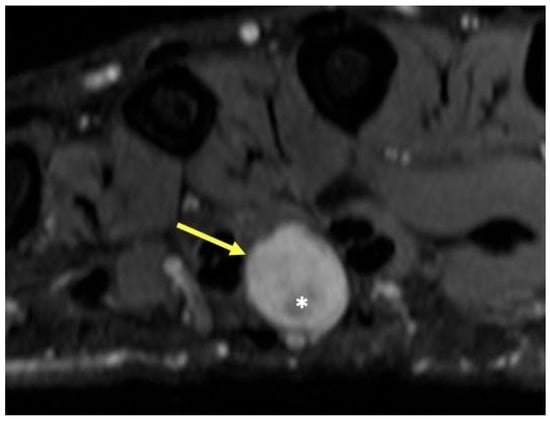

2.4.2. Radiographic Appearance

- Ahlawat, S.; Fayad, L.M. Imaging cellularity in benign and malignant peripheral nerve sheath tumors: Utility of the “target sign” by diffusion weighted imaging. Eur. J. Radiol. 2018, 102, 195–201. [Google Scholar] [CrossRef]